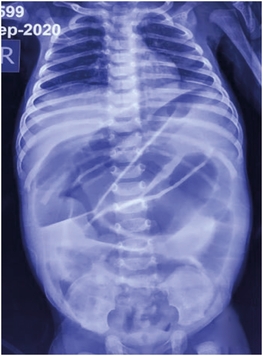

A 40-days old female infant was brought to our emergency room with complaints of progressively increasing abdominal distension for 10 days associated with bilious vomiting. The child was born at term via normal vaginal delivery, cried immediately after birth, and had a normal perinatal course. On initial examination, the baby was lethargic, dehydrated with pulse rate of 164/min, blood pressure of 64/42 mm Hg. The abdomen was grossly distended with shiny abdominal skin, dilated veins, and visible bowel peristalsis. Blood investigations were suggestive of elevated sodium (158 meq/L), low potassium (3.4 meq/L) and elevated urea (60 mg/dL) which were suggestive of dehydration. An abdominal X-ray showed dilated small bowel loops with multiple air-fluid levels (Fig. 1). After adequate resuscitation, the baby was taken up for emergency surgery in view of persistently high bilious aspirates with band obstruction, volvulus as our main differentials. On exploratory laparotomy, the whole small bowel was dilated till ileo-caecal junction. On careful palpation, a 3.5×3.5 cm firm mass was palpable in the caecum causing the luminal obstruction (Fig. 2A). The ileo-caecal segment was resected and ileo-ascending colon anastomosis was done. The cut section of the specimen showed a 3×3 cm cyst in the caecum with mucoid content (Fig. 2B). The postoperative period was uneventful and the child was discharged on the seventh day. Histopathology of the resected specimen was suggestive of enteric DC lined by columnar epithelium with ulcerated mucosa. At 1-year follow-up, the child had no complaints and is gaining weight adequately.

Fig. 1

Abdominal X-ray showing grossly dilated small bowel loops with paucity of rectal gas.